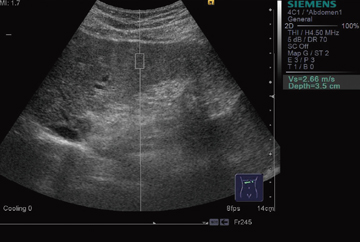

■ 組織硬度の絶対数値測定 ─ Virtual Touch Tissue Quantification

生体内部で横波の弾性波(shear wave)を発生させ,その速度の値を組織硬度の固有値とする。shear wave速度が速いほど,組織が硬いことを意味している。地質調査で実用化されている弾性波探査 法の原理である。シーメンスの開発した“Virtual Touch Tissue Quantification”では,shear waveの発生に収束超音波パルスによる音響放射力の作用(Acoustic Radiation Force Impulse:ARFI)を用い,測定ポイントを1か所に限局することによって,測定の安定性と精度を向上させている(図2)。